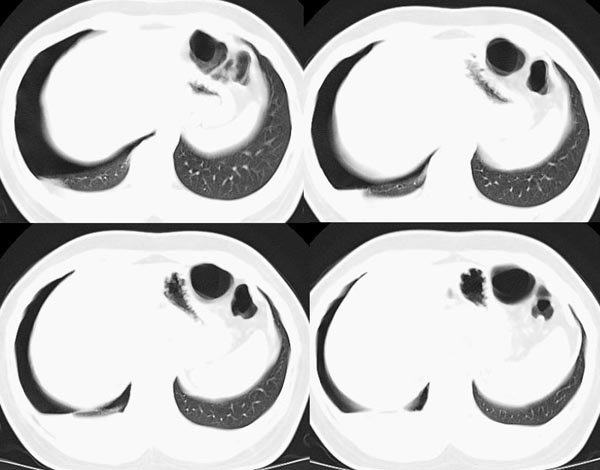

m21y既往体健,否认结核、支扩等病史;1周前患上感,无明显咳嗽,自觉无明显不适。单位体检透视时发现右侧液气胸!cr及ct如下(肺组织窗:l:-598hu w:1132hu):请大家会诊!!

右侧巨大含气囊性病变,壁薄、光整、其外侧见气体。右肺压迫性肺不张、胸腔内见少量积液。纵隔向左侧移位。左肺未见异常。诊断:1.右侧含气肺囊肿(先天性)。2.右侧液气胸。(少量液体)3.右肺压迫性肺不张。我也遇见一例这样的病人。女性。股骨外伤就诊。常规胸片发现右侧囊性病变。